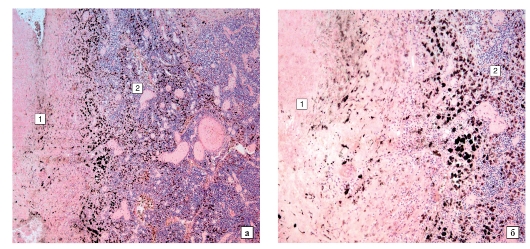

Микроскопический взгляд на мишитарный туберкулез легкого: фотодокументация

Раздел: Снимки-откровения